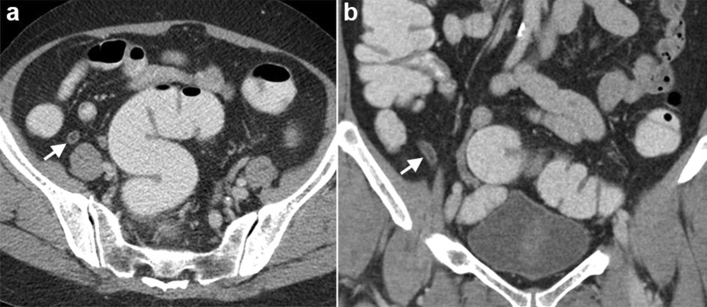

The appendicitis group had a larger maximal diameter (p = 0.005) and thicker appendiceal wall (p = 0.014) than the patients without appendicitis (Fig. 1). There was moderate agreement for measurement of maximal diameter and good agreement for measurement of wall thickness. Variable agreement of CT findings between two readers was noted, with peritoneal thickening had the lowest agreement and gas in appendix lumen had the highest agreement. The data is shown in Table 2.

Figure 1.

Acute appendicitis in a 65-year-old female with Alvarado score of 7. Cross-sectional (a) and coronal (b) computed tomography scan showing enlarged appendiceal diameter and wall thickening (arrows).